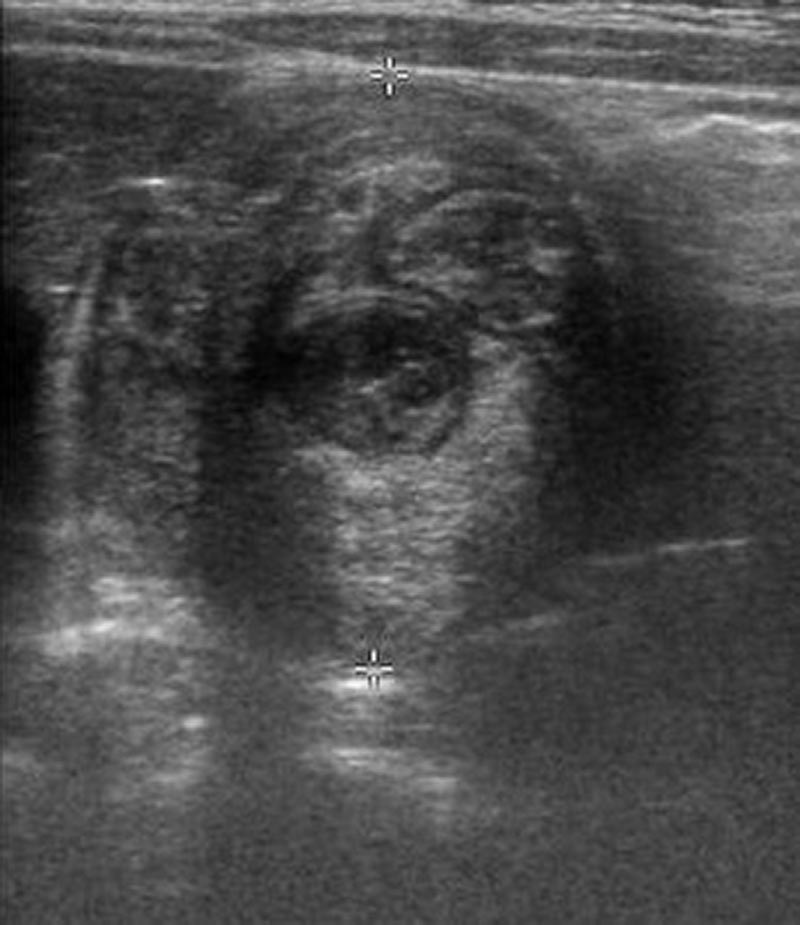

10-month-old male infant presents to the ED by EMS with vomiting and altered mental status (AMS). Infant arrives to the ED awake but poorly interactive. Ultimately, the infant will be diagnosed with intussusception and hypovolemic shock based on the history, physical exam and ultrasound findings. Learners are expected to establish a differential diagnosis of AMS appropriate for an infant, demonstrate appropriate resuscitative interventions, and use appropriate imaging and labs to help identify the cause of AMS.